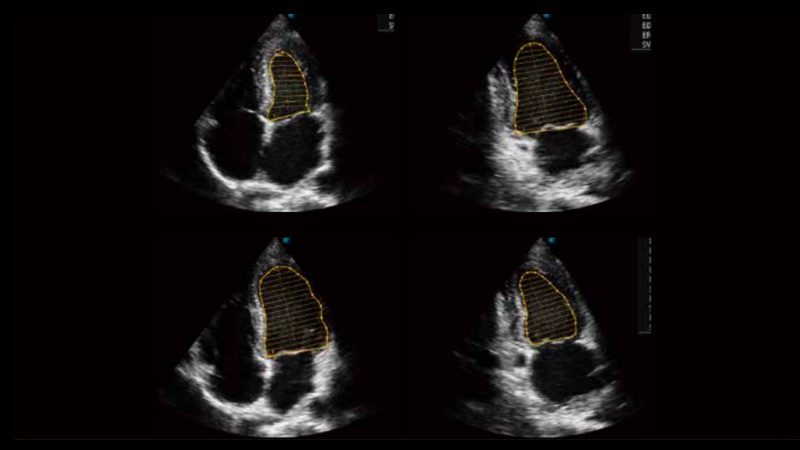

自动识别收缩和舒张末期心肌内膜,自动计算射血分数EF值。